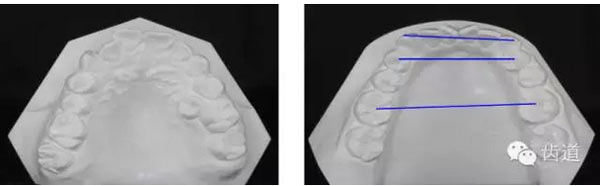

上牙弓:尖圓形,25腭側(cè)完全錯(cuò)位,26前移

上牙弓擁擠度9mm;下牙弓擁擠度7mm;

Pont指數(shù):

第一前磨牙指數(shù)(82.16±4.22):82.72

第一磨牙指數(shù)(63.36±3.64):64.97

前段寬度 | 中段寬度 | 后段寬度 | |

上牙列 | 31.6mm | 33.2mm | 41.8mm |

下牙列 | 27.6mm | 28.9mm | 39.6mm |

………提示上牙弓較下牙弓狹窄

治療后模型

橫向不調(diào):牙弓寬度輕度不調(diào)的解決在于上頜適當(dāng)?shù)臄U(kuò)弓與后退左上牙列,以及下頜適當(dāng)?shù)目s弓與下磨牙前移,矯治后上頜磨牙寬度由41.8mm變?yōu)?3.1mm,下頜磨牙寬度由39.6mm變?yōu)?7.8mm。